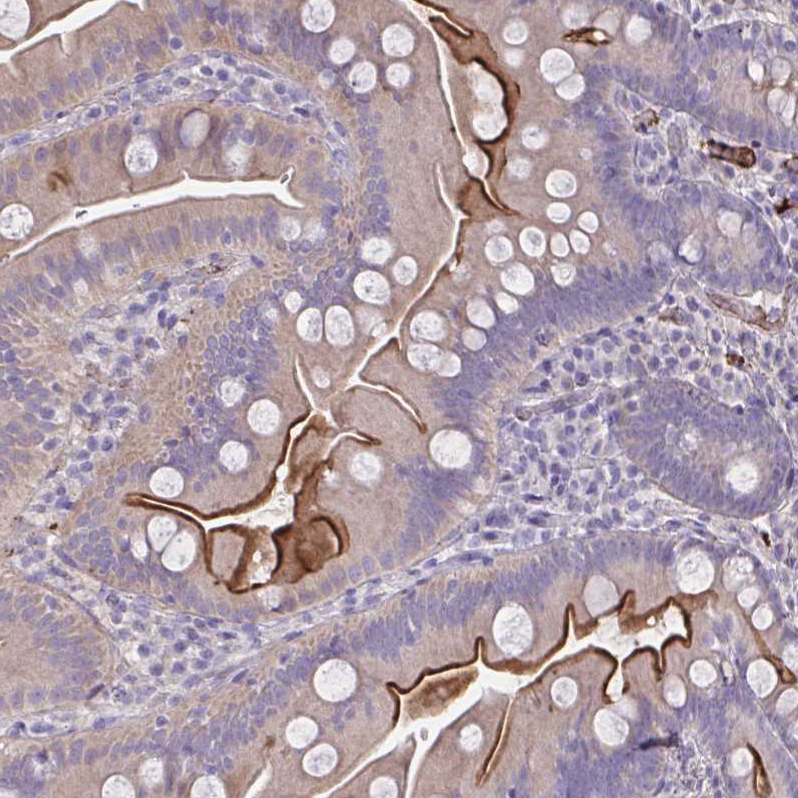

Immunohistochemical staining of human small intestine shows strong luminal membranous positivity in glandular cells.